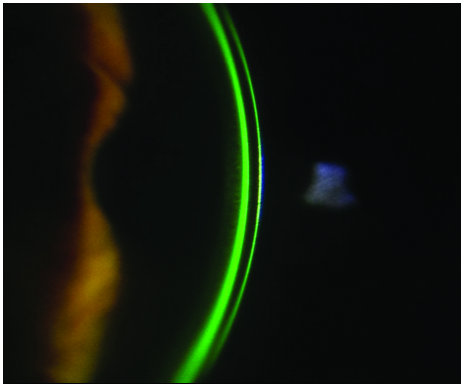

Sin ningún lugar a dudas, el examen biomicroscópico bajo la lámpara de hendidura es el primer paso en la evaluación diagnóstica del ojo seco.

La evaluación del menisco lagrimal y de las características anatómicas y funcionales de la superficie ocular es fundamental en el desarrollo de los pasos diagnósticos de la enfermedad.

Debe incluirse además el examen biomicroscópico de los párpados y anexos palpebrales, así como también de la arquitectura de la superfcie ocular.

La tríada clásica (por mí denominada eterna) compuesta por el test de Schirmer, las tinciones y el BUT nos acompañan hasta nuestros días (Fig. 8).

Figura 8: La tríada eterna

La tinción con fluoresceína o solución de Grant permite evaluar la superficie epitelial de la córnea y determinar la presencia o no de soluciones de continuidad y lesiones.

Dividimos la córnea en cinco cuadrantes y según el grado tincional le otorgamos un valor de cero a tres, al mismo tiempo que podemos diferenciar macro o micropuntillado sobre la córnea.

La tinción con rosa de bengala o lisamina verde sobre la superficie epitelial conjuntival determina la presencia o no de mucus. Dividimos la conjuntiva en seis cuadrantes y le otorgamos al grado tincional un valor de cero a tres para su evaluación.

Estos dos colorantes permiten diferenciar los cuadros lacrimodeficientes de cuadros evaporativos según tiñan la zona expuesta o la zona no expuesta conjuntival.

Con el rosa de bengala o la lisamina verde se puede determinar además el grado de fricción palpebral que se expresa al evertir el párpado superior y observar si el colorante tiñe el borde interno palpebral (Fig. 9).

Figura 9: Tinción con lisamina zona de fricción